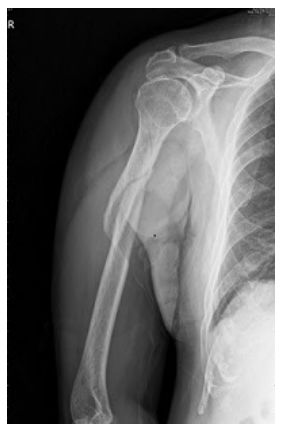

52 70歲男性騎機車自摔右手撐地,右上臂腫脹瘀青明顯無法用力,X光如附圖所示,下列敘述何者正確? ①X光顯示右側肱骨幹骨折 ②該處骨折為橫斷性骨折 ③該骨折易併發尺神經受損 ④該處骨折因容易發生骨折延遲癒合或不癒合 (A)①③ (B)②③ (C)①④ (D)②④